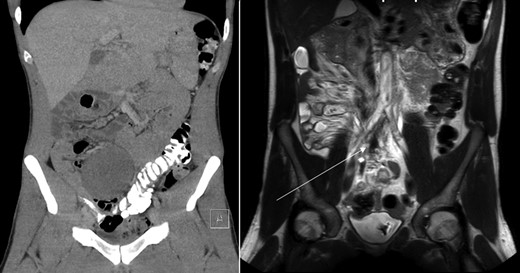

Axial view of CT-abdomen (left) and MRI-abdomen 1 year later. A pear-shaped lesion is seen on the CT, which regressed as seen on the MRI (arrow).

Sonography after three months showed a reduction in size to 9.4 × 5.4 cm2. On request of the patient, who was anxious of having a tumor which was treated conservatively, a second opinion was performed at an University Medical Center. They acknowledged the conservative approach and advised follow up with magnetic resonance imaging (MRI) 1 year after diagnosis. This MRI showed regression of the tumor with a small residue of 2.2 × 1.2 × 1.9 cm2 (Figs 1 and 2) along the right ureter and a minimal hydronephrosis of the right kidney without loss of renal function. A second MRI 6 months later and a third MRI 1 year later showed persisted regression without hydronephrosis. Both scans showed no other masses. The patient did not develop any symptoms during follow up.